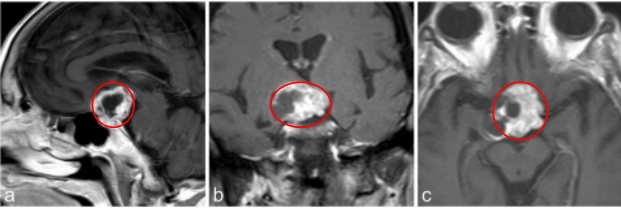

患者术前情况:62岁女性,患者35年前有垂体大腺瘤复发史,随后接受放射治疗复发性肿瘤引起的侧性眼球麻痹的进行性复视。

术后影像片子显示肿瘤切除干净: